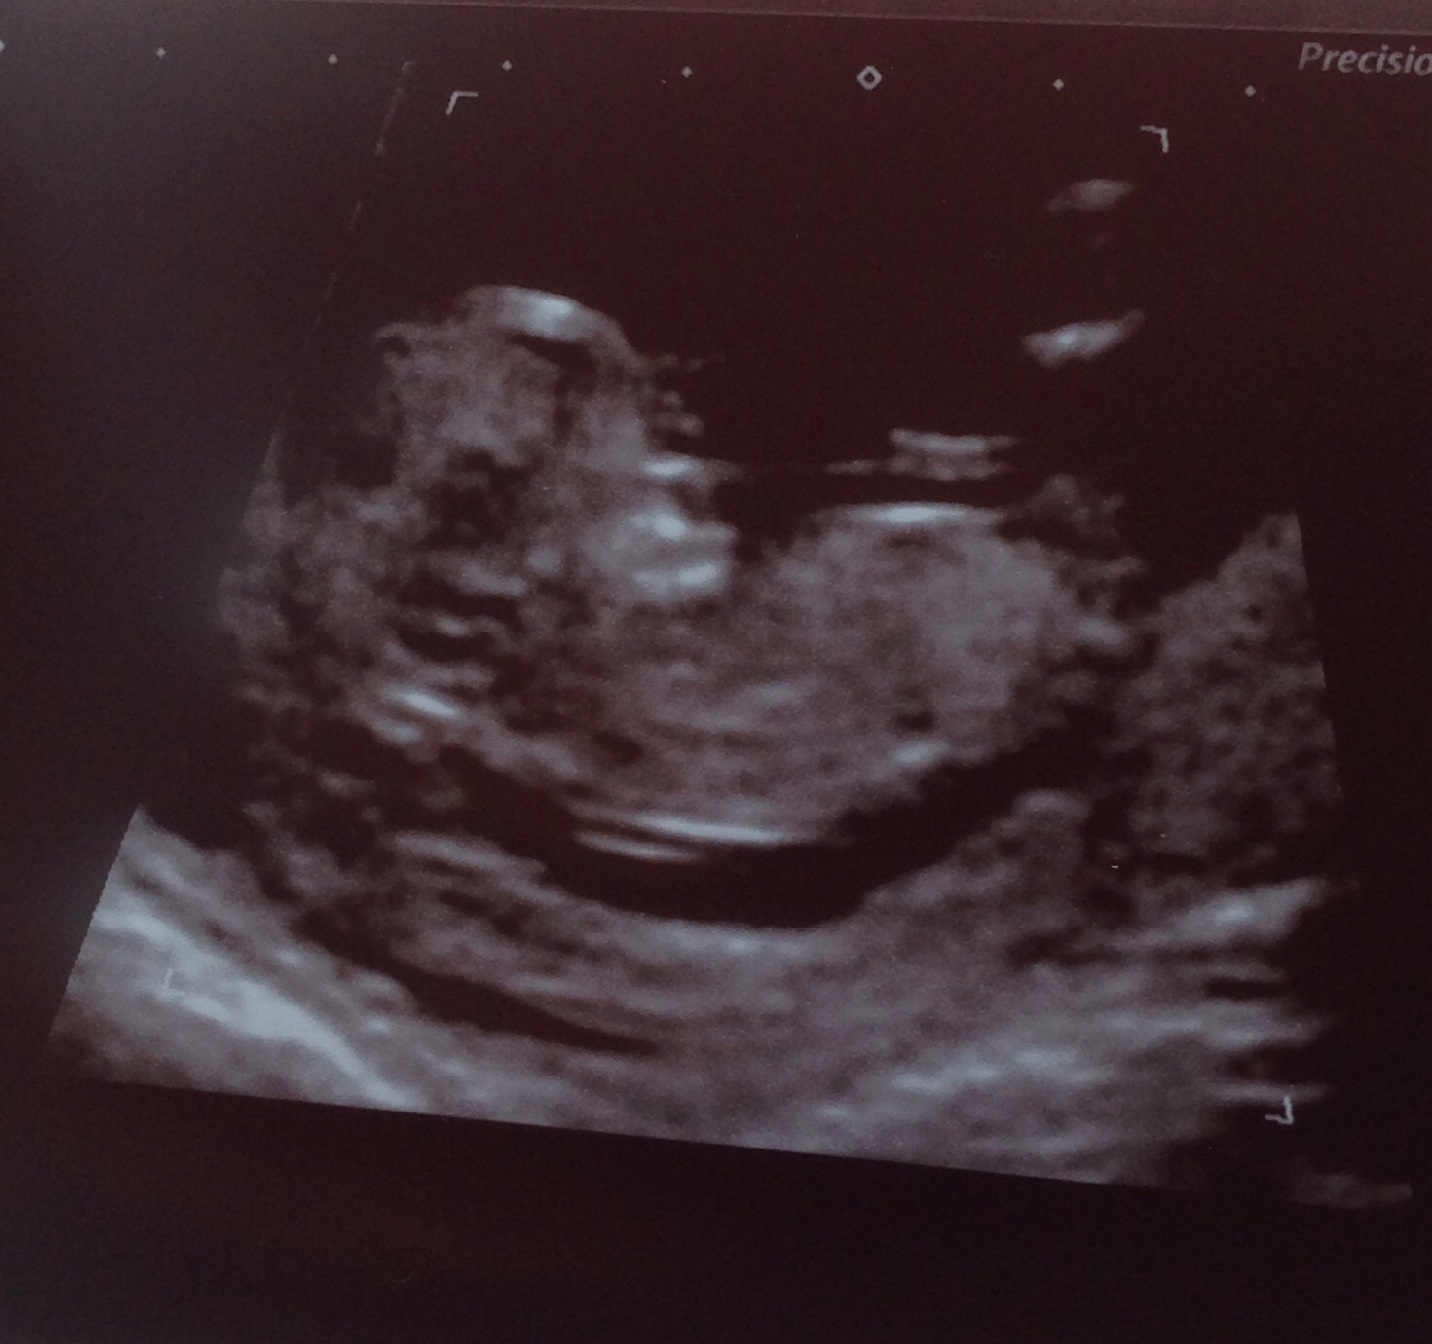

Hi just wondering if anyone would like to guess what sex my baby is, can't tell whether the lines are a nub?? Not quite sure where I'm supposed to be looking! Also is the skull theory best from the 12 week scan or the 20 week?Attachment 20778

Thanks xx